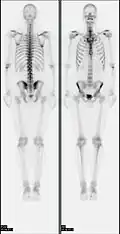

- 2D: Сцинтиграфия (от лат. «знать») — это использование внутренних радионуклидов для создания двухмерных изображений.

Сканирование костей всего тела с помощью ядерной медицины. Сканирование костей всего тела в ядерной медицине обычно используется для оценки различных патологий, связанных с костями, таких как боли в костях, стрессовые переломы, доброкачественные поражения костей, инфекции костей или распространение рака на кость. -

Сканирование перфузии миокарда с помощью ядерной медицины с таллием-201 для изображений покоя (нижние ряды) и Tc-Sestamibi для изображений стресса (верхние ряды). Сканирование перфузии миокарда с помощью ядерной медицины играет ключевую роль в неинвазивной оценке ишемической болезни сердца. Исследование не только идентифицирует пациентов с ишемической болезнью сердца; он также предоставляет общую прогностическую информацию или общий риск неблагоприятных сердечных событий для пациента. -